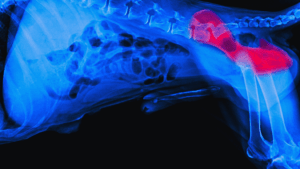

Heatstroke is a life-threatening condition that can affect dogs and cats, causing their body temperature to rise to dangerous levels. Unlike humans, these animals cannot regulate their body temperature by sweating, making them more susceptible to heatstroke. It is important for pet owners to understand the causes and early signs of heatstroke to ensure the well-being of their furry companions.

Dogs release excess body heat primarily through panting, as they cannot sweat like humans. However, panting may not always be enough to cool them down, especially during hot summer months. Certain breeds, such as Bulldogs, Pugs, and Shih Tzus, are more sensitive to heat due to their broad skulls and shorter limbs. Dogs with long hair or thick fur coats, as well as puppies and senior dogs, also have a higher risk of developing heatstroke. It is important to understand that all dogs are at risk of heatstroke under intense heat, regardless of breed.

Dogs regulate their body temperature by panting. During panting, dogs open their mouths wide, allowing air to flow rapidly over their tongue and the moist tissues of their nasal passages, throat, and lungs. This evaporative cooling helps to reduce their body temperature. However, panting may not be sufficient to cool down a dog in extremely hot conditions or if they are unable to access fresh air.

In addition to panting, dogs also dissipate heat through their paw pads. Paw pads have a large number of sweat glands that release moisture, allowing heat to be released through evaporation. However, this method is not as effective as panting and is more useful for small temperature adjustments rather than significant cooling.